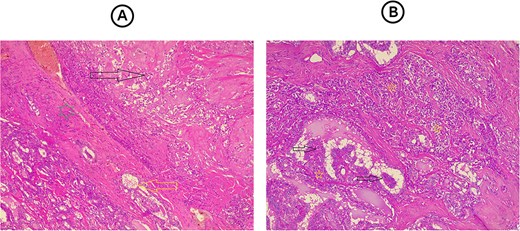

Total thyroidectomy with bilateral central neck dissection was performed through a collar incision. Both recurrent laryngeal nerves and the parathyroid glands were achieved through meticulous dissection and careful identification of anatomical structures. Although nerve monitoring was not employed, the recurrent laryngeal nerves were preserved by maintaining their anatomical integrity and ensuring minimal manipulation. The parathyroid glands were preserved by protecting their blood supply and avoiding unnecessary handling. Despite the challenges posed by the tumor’s proximity to these structures, the careful surgical technique allowed for their successful preservation, minimizing the risk of postoperative complications. The excised tissue underwent histopathological examination (HPE), which revealed bilateral MTC with conventional PTC in the left lobe, consistent with a collision tumor, and admixture of both cancer cell types within one of the lymph nodes (Fig. 1). Gross examination revealed bilateral MTC in the right and left lobes, with a well-defined 1.5 cm nodule in the right lobe and a 2.5 cm nodule replacing the left lobe. Histologically, the MTC was multifocal and bilateral, while the PTC (0.5 cm) was unifocal in the left lobe. Both tumors showed lymph-vascular and perineural invasion, and regional lymph node involvement was present in 10 out of 39 nodes, The HPE revealed that one of the Delphian lymph nodes contained metastatic deposits from both tumors while other lymph node metastasis were all from the MTC, with extra-nodal extension and osseous metaplasia observed in the largest deposit. The collision tumor was confined to the thyroid capsule, with no evidence of extrathyroidal extension or necrosis.

(A) Section from the thyroid tumor showing an area composed of dyscohesive plasmacytoid cells with salt-pepper chromatin and presence of eosinophilic material in between them representing amyloid material (dark arrow), while bellow it, separated by a fibrous band (green star), there is an area showing follicular epithelial cells, with nuclear features of papillary thyroid carcinoma (yellow arrow). Hematoxylin and eosin stain, 4 × 10. (B) Section from the lymph node reveal both tumor components mixed with each other, area showing papillary structures that covered by follicular epithelial cells with nuclear features of papillary thyroid carcinoma (dark arrows) with other area composed of solid nests of dyscohesive cells that representing the medullary thyroid carcinoma. Hematoxylin and eosin stain, 4 × 10.